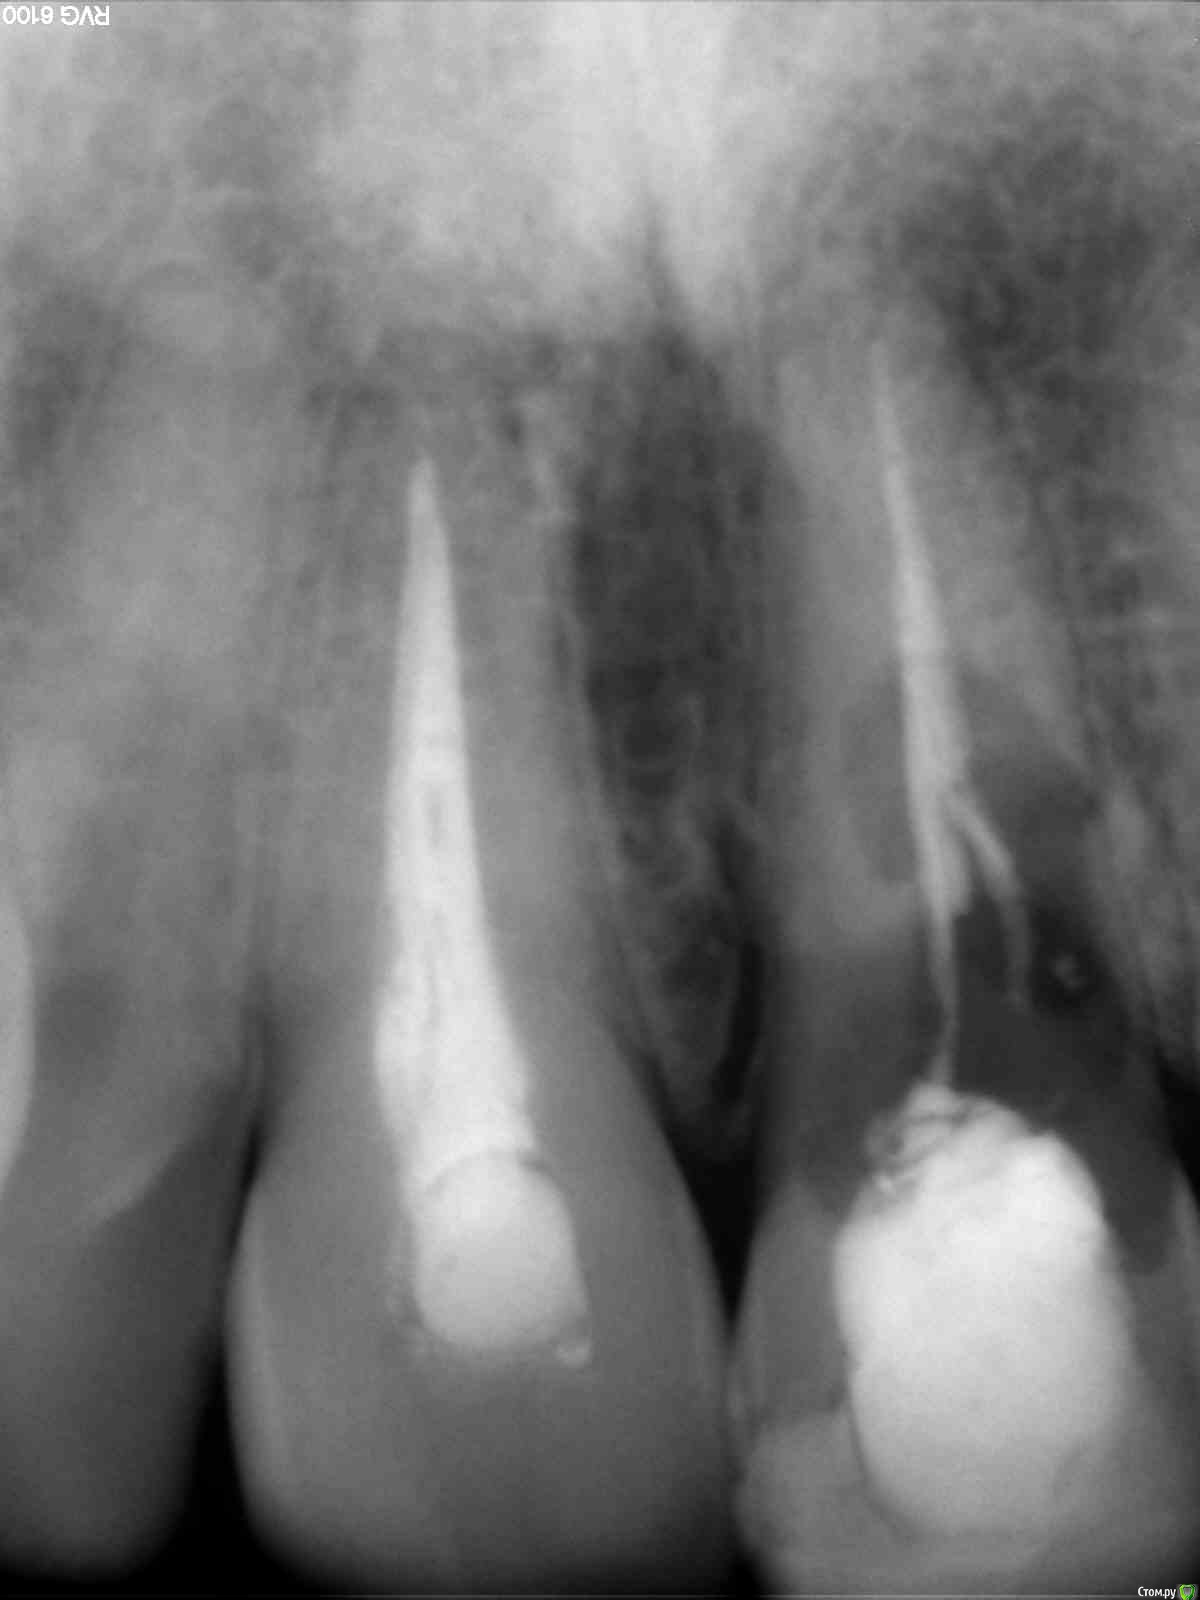

ricoo Опубликовано 21 мая, 2016 Поделиться Опубликовано 21 мая, 2016 Добрый день.Очень давно была травма передних зубов но с одним из них всё стало развиваться по плохому сценарию. Было несколько лечение, чистка каналов, пломбирование. всё это повторялось и привело к нынешней ситуации. Хирург предлагает удаление как можно быстрее с использованием плазмы крови. по его мнению проходит разрушение костной ткани и постоянный имплант будет сложно поставить если не предпринимать никаких действий.Хотелось бы услышать мнение со стороны. возможные прогнозы и риски при дальнейшем развитии событий. в каком состоянии костная ткань нужна ли пересадка? как в этом случае будет происходить удалении, возможны ли минимальные повреждения десны? какой имплант выбрать?Спасибо. Ссылка на комментарий

ricoo Опубликовано 21 мая, 2016 Автор Поделиться Опубликовано 21 мая, 2016 (изменено) тут речь идет об удалении и немедленной имплантации.оттягивать с удалением не рекомендуется.Да, я уже почти готов к этому. Если возможно что то еще прокоментировать по этому снимку, буду рад услышать это. особенно интересует как могут развиваться дальнейшие события в этом случае. Я понимаю что удаление не простое, зуб сломается и нужно будет выпиливать. оставшиеся отверстие заполнят плазмой крови для лучшего восстановление костной ткани. дальнейшие лечение пока подробно не обсуждалось с врачом. что можно сказать о состоянии костной ткани и о крайних зубах? один из стоматологов дал свой комментарий и предположил: "на мой взгляд стоматолога, состояние костной ткани вокруг проблемного зуба ( имеется деструкция периодонтальной связки и кости) -есть относительное противопоказание к имплантации. Это во- первых."с предложением отказаться от импланта. так же он пореконмендовал "Второй зуб необходимо перелечить, на верхушке уже начались деструктивные процессы, пока можно его спасти, это само не рассосется, не надейтесь." Интересно услышать иное мнение если оно есть. я воспринимаю это исключительно лишь как информацию в справочных целях. Изменено 21 мая, 2016 пользователем ricoo Ссылка на комментарий

Bier Опубликовано 22 мая, 2016 Поделиться Опубликовано 22 мая, 2016 какие комментарии по такому снимку?имплантат нужно ставить сразу в день удаления зуба, плазма - это так, она сама по себе ничего не меняет и кость не восстанавливает.Зуб надо удалить аккуратно, это возможно. Ссылка на комментарий

Bier Опубликовано 22 мая, 2016 Поделиться Опубликовано 22 мая, 2016 Разве костная ткань позволяет установить одномоментно имплант и почему это следует делать сразу а не через несколько месяцев? какие могут быть деформации с десной если не ставить имплант какоето время?на мой взгляд позволяет.Если сразу не поставить получите еще бОльшую атрофию и бОльшие проблемы с десной. 1 Ссылка на комментарий